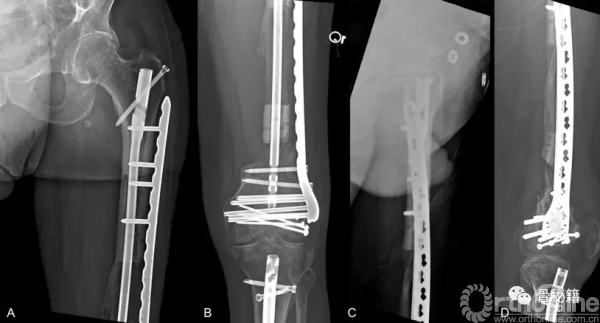

54岁男性,开放骨折,摩托车伤

股骨前方8X5cm的伤口,13-cm的骨缺损

股骨髁远端粉碎骨折

怎么办??

首先,感染控制住了,更换了内固定+磁力髓内钉+一组滑轮

由于远端大量骨缺损,先行了Liss钢板固定远端

同时给与近端股骨磁力髓内钉,同时进行截骨

通过漫长的搬移,终于骨折断端接触了

更换全长的髓内钉来进行稳定骨折

术后13个月随访,骨搬移矿化良好

一根可延长髓内钉,就完成了整个手术

不用带外架,患者耐受度高

力线完美维持